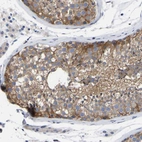

Immunohistochemical staining of human lymph node shows strong cytoplasmic positivity in non-germinal center cells.